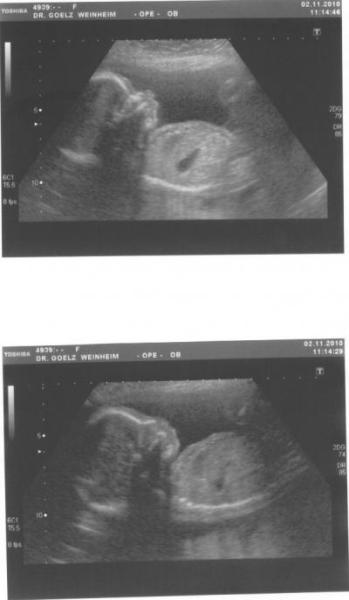

Halli Hallo, ... mein Besuch beim FA viel heut zwar etwas nüchtern aus, aber es war wichtig das alles in Ordnung ist. Ich bin eine vorbildliche Schwangere, mit ein paar durchaus üblichen Zipperlein und sonst ist alles easy. Madame war heute sehr fotogen, so das er den Rest von letzten mal schnell "aufarbeiten" (so nannte er das) konnte. Herz, Zwerchfell, Nabel-schnur und das Gesicht. Alles so wie es sein soll. Die Dame hat nun 444gund ist ca. 24cm groß. ja was will man mehr. Die zwei Bildchen hänge ich an, mit gefällt die Stupsnase so gut. Das nächste mal habe ich dann diesen Zuckerbelastungstest. Na schauen wir mal, hab gehört dass das Zeug grausigsüss schmecken soll. Zu blöd ich mag im Moment lieber saures. Ich wünsch euch allen noch eine schöne Woche, LG, Manu.

Bild zu Zurück vom FA... mit Profilbildchen! - Forum für März - Mamis

Schön, das alles ok ist mit Deinem Krümel. Sehr schönes Foto hast Du da.... glg

Toll das alles okay ist und das Bild ist auch toll.